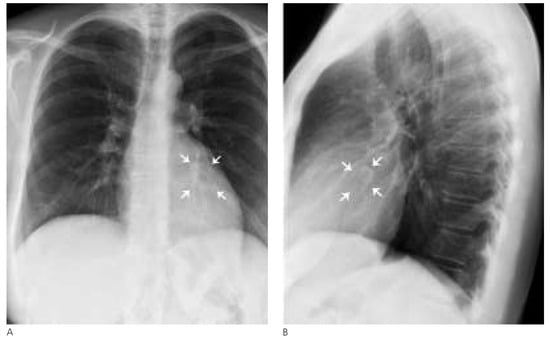

Eine Frau mit einer Intramyokardialen Verkalkung

Fallbeschreibung